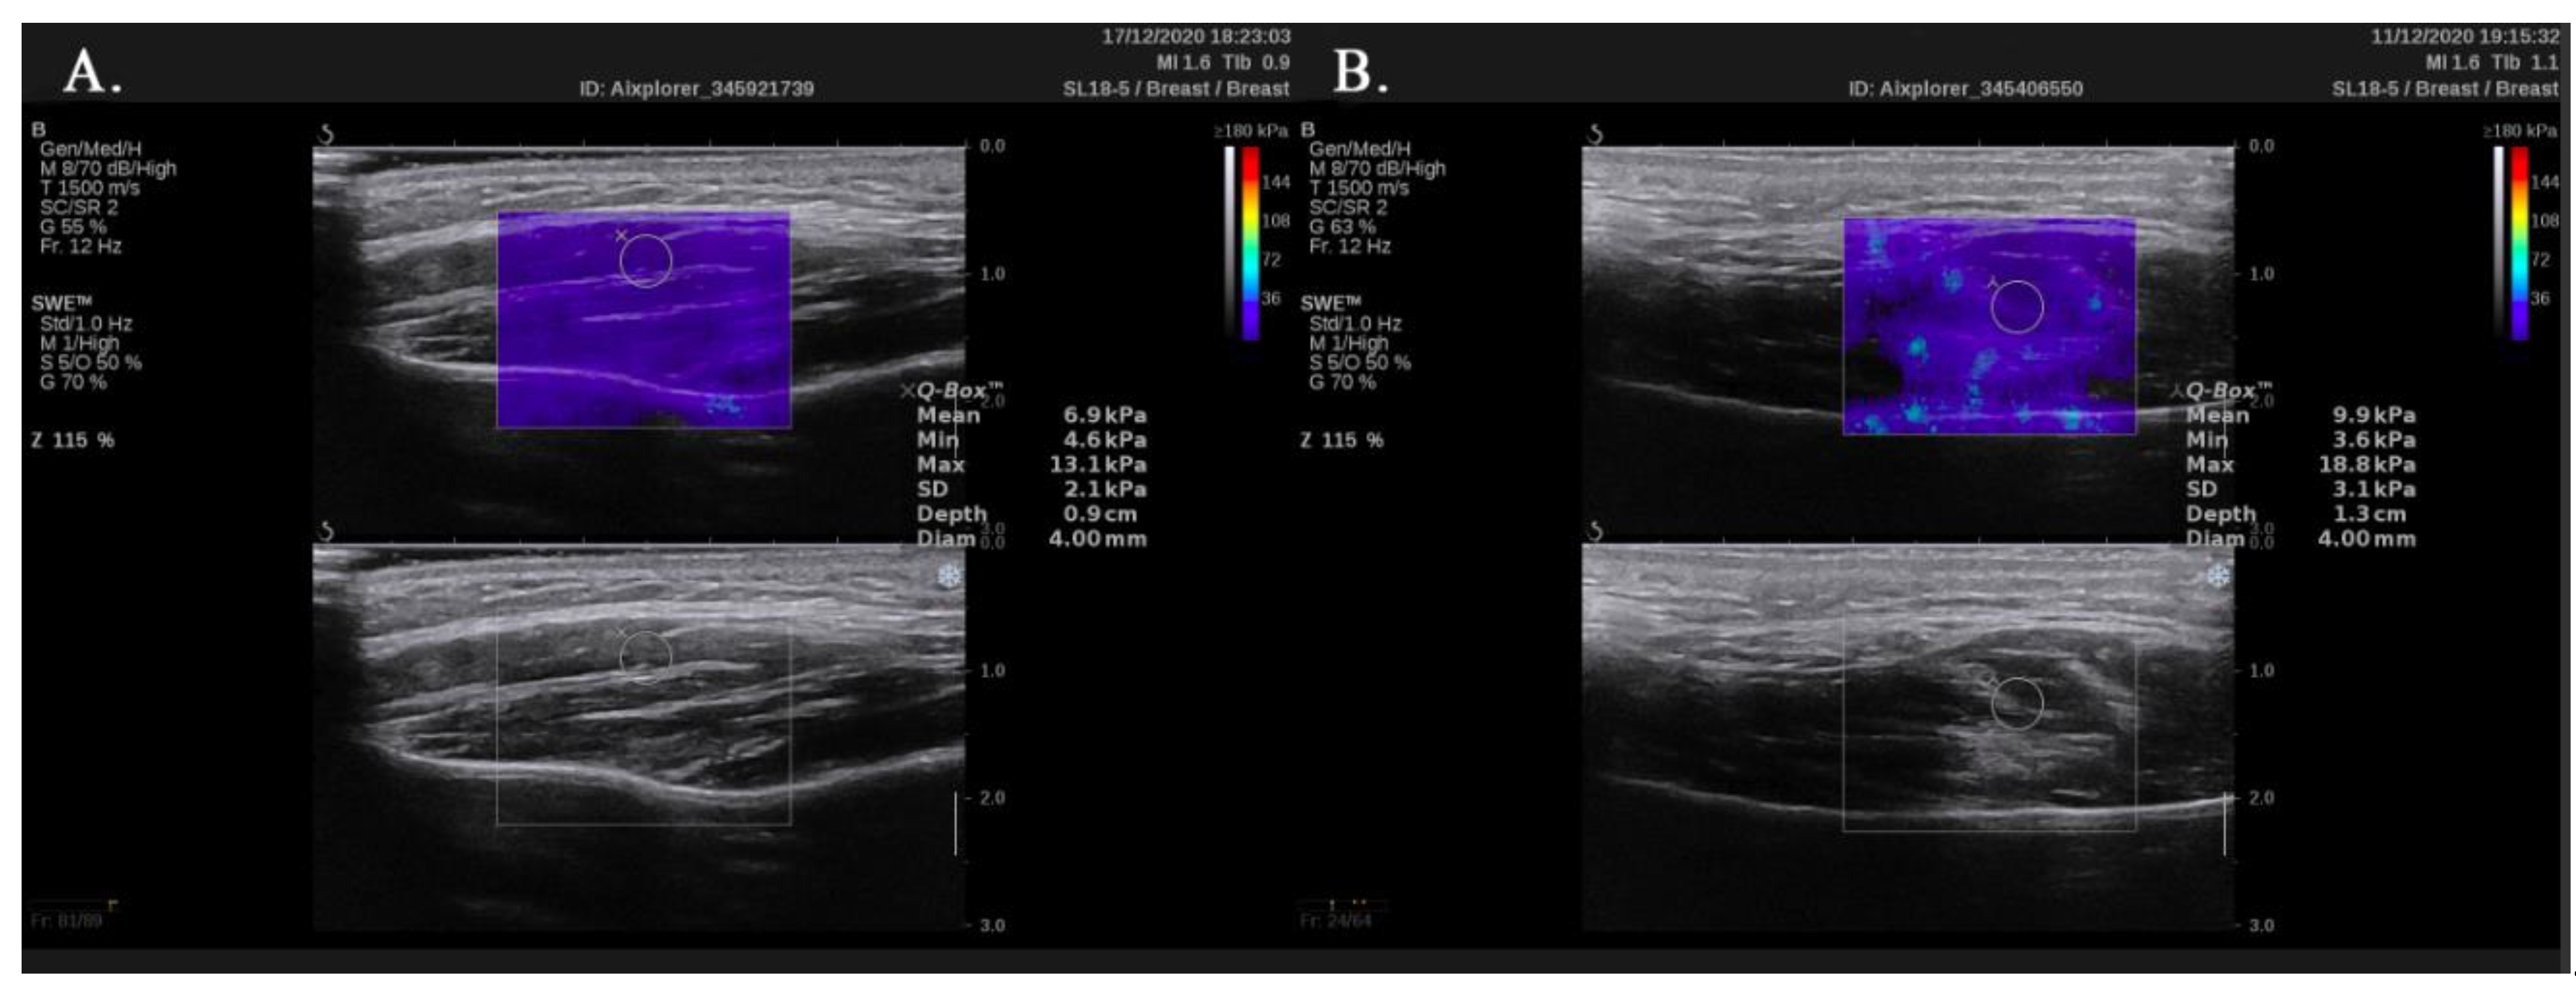

2. Materials and Methods

3. Results